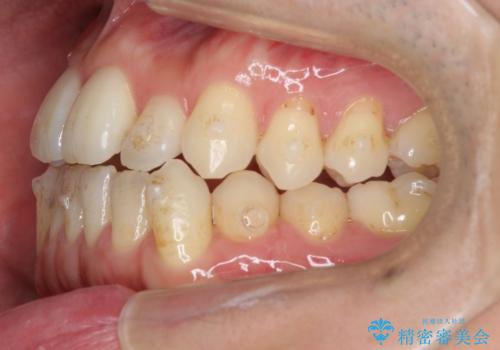

- 受け口を主訴に来院。

前歯の反対咬合でしたが、かみ合わせが、下顎が大きく前方にずれていました。

引っ込んでいる前歯の前方に下の犬歯が深く咬み込んでおり、また、奥歯のかみ合わせも受け口方向にずれ、骨格性の反対咬合も少々ありました。

上の前歯を前方に出すだけでは治療ができないため、ミニスクリューを用いて下の奥歯を後ろに送っています。

また、下の前歯を0.3mmずつIPRしています。